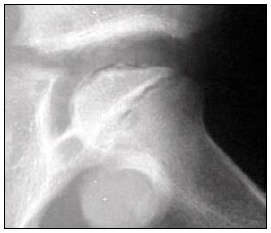

“Criança, sexo masculino, 5 anos de idade, apresenta claudicação na marcha e dificuldade ao fazer a rotação interna do quadril. Apresenta o exame de imagem do quadril na incidência de Lauenstein.”

De acordo com o exposto, trata-se provavelmente de